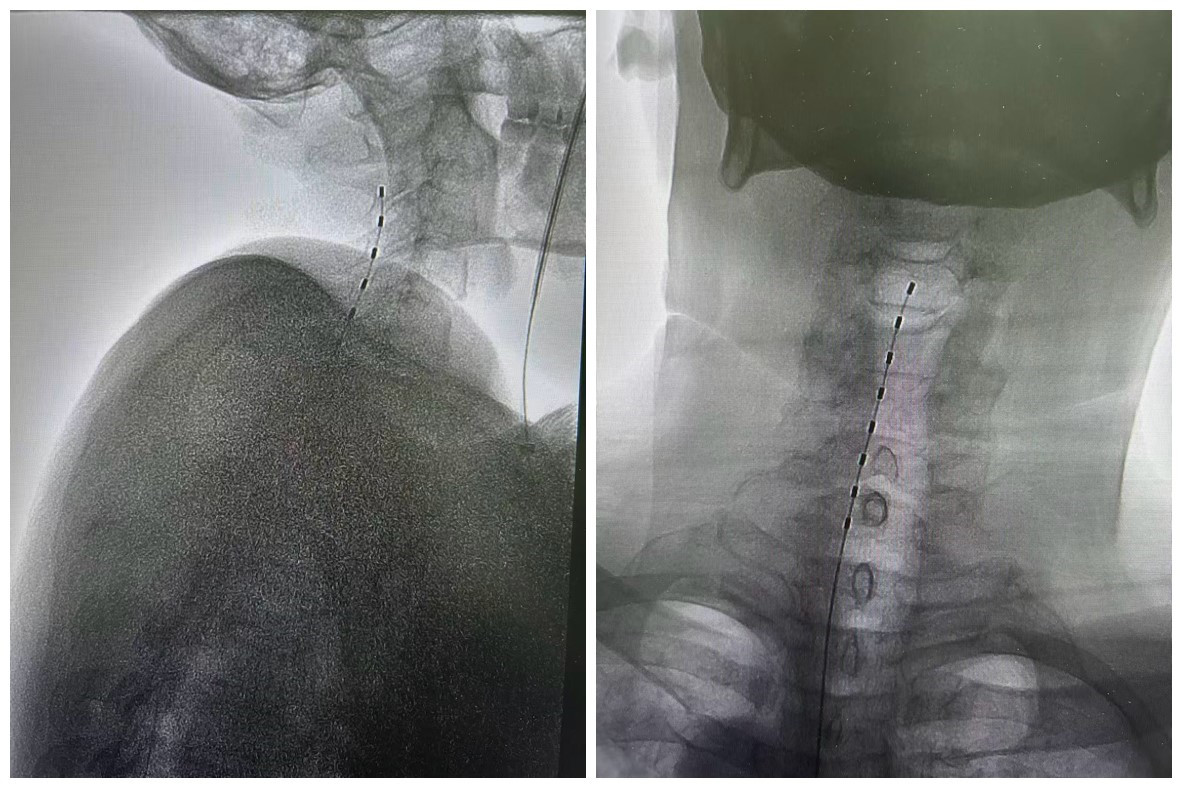

电极植入后影像

三个月前患者因脑出血遗留左侧肢体偏瘫,同时伴随左上肢肌张力增高及肢体疼痛,严重影响生活质量。神经外科团队经详细评估后,决定采用脊髓电刺激技术为其治疗。手术中,池超超副主任医师凭借精湛技术,通过穿刺方式精准植入电极,全程微创、创伤小。电极成功到位并开机后,患者当即反馈左上肢疼痛明显减轻,肌张力增高症状也同步缓解,治疗效果佳。